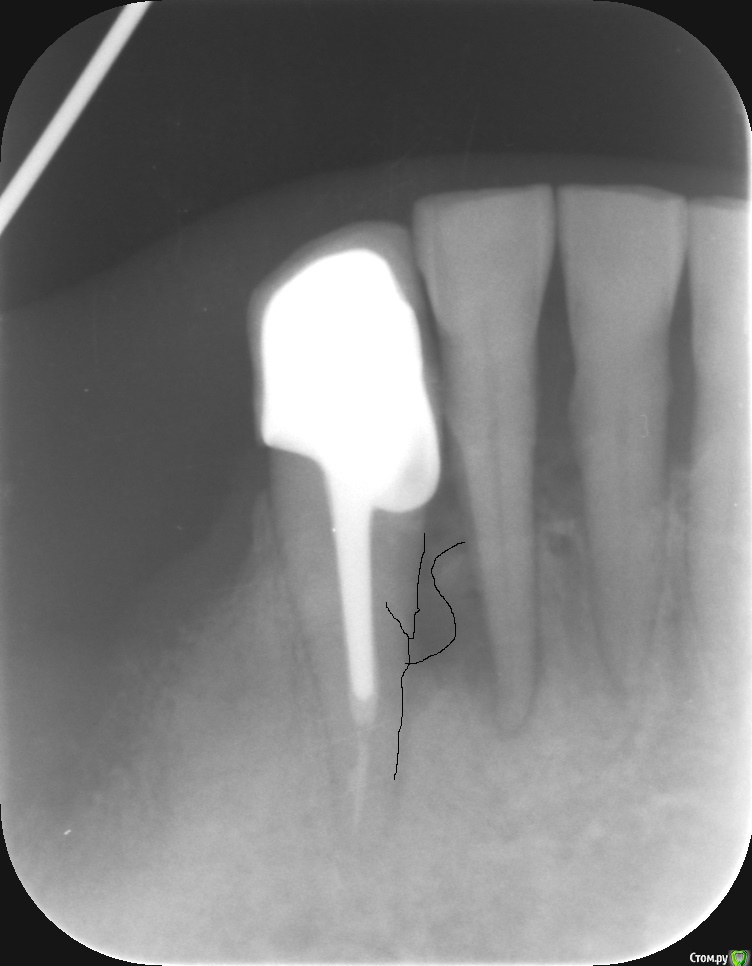

jsvc Опубликовано 18 апреля, 2017 Автор Поделиться Опубликовано 18 апреля, 2017 (изменено) Я конечно не стоматолог, но как мне кажется прицельный снимок однозначно указывает на то что источником воспаления является 43 (см. форму очага воспаления во вложении).А увеличенная периодонтальная щель у 42 это следствие инфицирования периодонта из очага воспаления. Изменено 18 апреля, 2017 пользователем jsvc Ссылка на комментарий